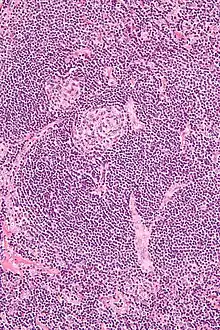

| Micrograph of lymph node biopsy demonstrating hyaline vascular features consistent with Castleman disease | |

The microscopic appearance (histology) of biopsied tissue from an enlarged lymph node must demonstrate a constellation of features consistent with Castleman disease. There are three patterns of characteristic histologic features associated with UCD:[7]

- Hyaline vascular - regressed germinal centers, follicular dendritic cell prominence or displasia, hypervascularity in interfollicular regions, sclerotic vessels, prominent mantle zones with an “onion-skin” appearance.

- Plasmacytic – increased number of follicles with large hyperplastic germinal centers and sheetlike plasmacytosis (increased number plasma cells).

- Mixed - features of both hyaline vascular and plasmacytic patterns

UCD most commonly demonstrates hyaline vascular features; however, plasmacytic features or a mixture of both hyaline vascular and plasmacytic features may also be seen in UCD lymph nodes.[6] The clinical utility of subtyping Castleman disease by histologic features is uncertain, as histologic subtypes do not consistently predict disease severity or treatment response.[7]